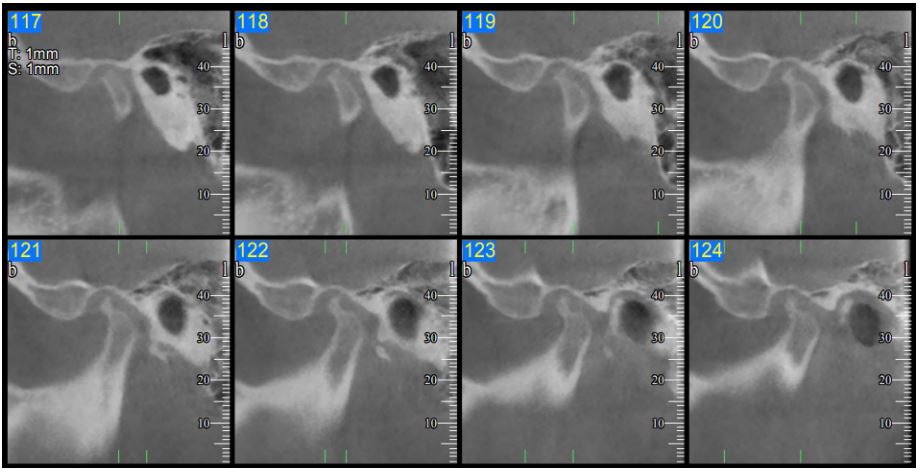

The clinical examination of the patient comprised of the palpation of the TMJ and the main muscles of the stomatognathic system (Table 1). During the TMJ examination, the maximum opening was 28 mm and painful (Figures 2 and 3). During opening the jaw deviated to the left. Finally, the maximum laterotrusion to the left was limited to 5 mm, in contrast to 10 mm to the right, which is considered normal (Table 2). An important clinical finding was the presence of crepitation sound from the left TMJ, a pathognomonic sign of structural alterations of the joint.

Figure 2: The patient in maximum opening.

Figure 3: The maximum opening using the upper and lower incisor edges, as reference points was limited (28 mm, when the normal is >40 mm) and painful.